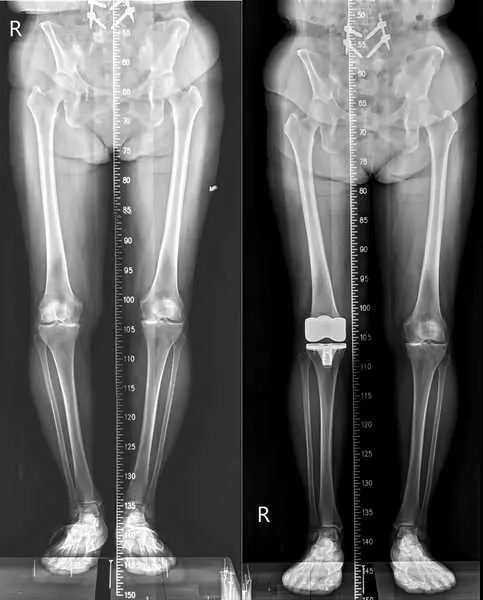

該名患者來到診間時,膝蓋疼痛異常,且因關節萎縮變形導致無法完全伸直。經 X 光檢測發現,患者右腳內側的關節面已完全磨損、上下關節幾乎貼合,屬最嚴重「第四期」的退化性膝關節炎症狀。

圖二:全人工膝關節置換手術術前(左),術後(右)X光對照圖。